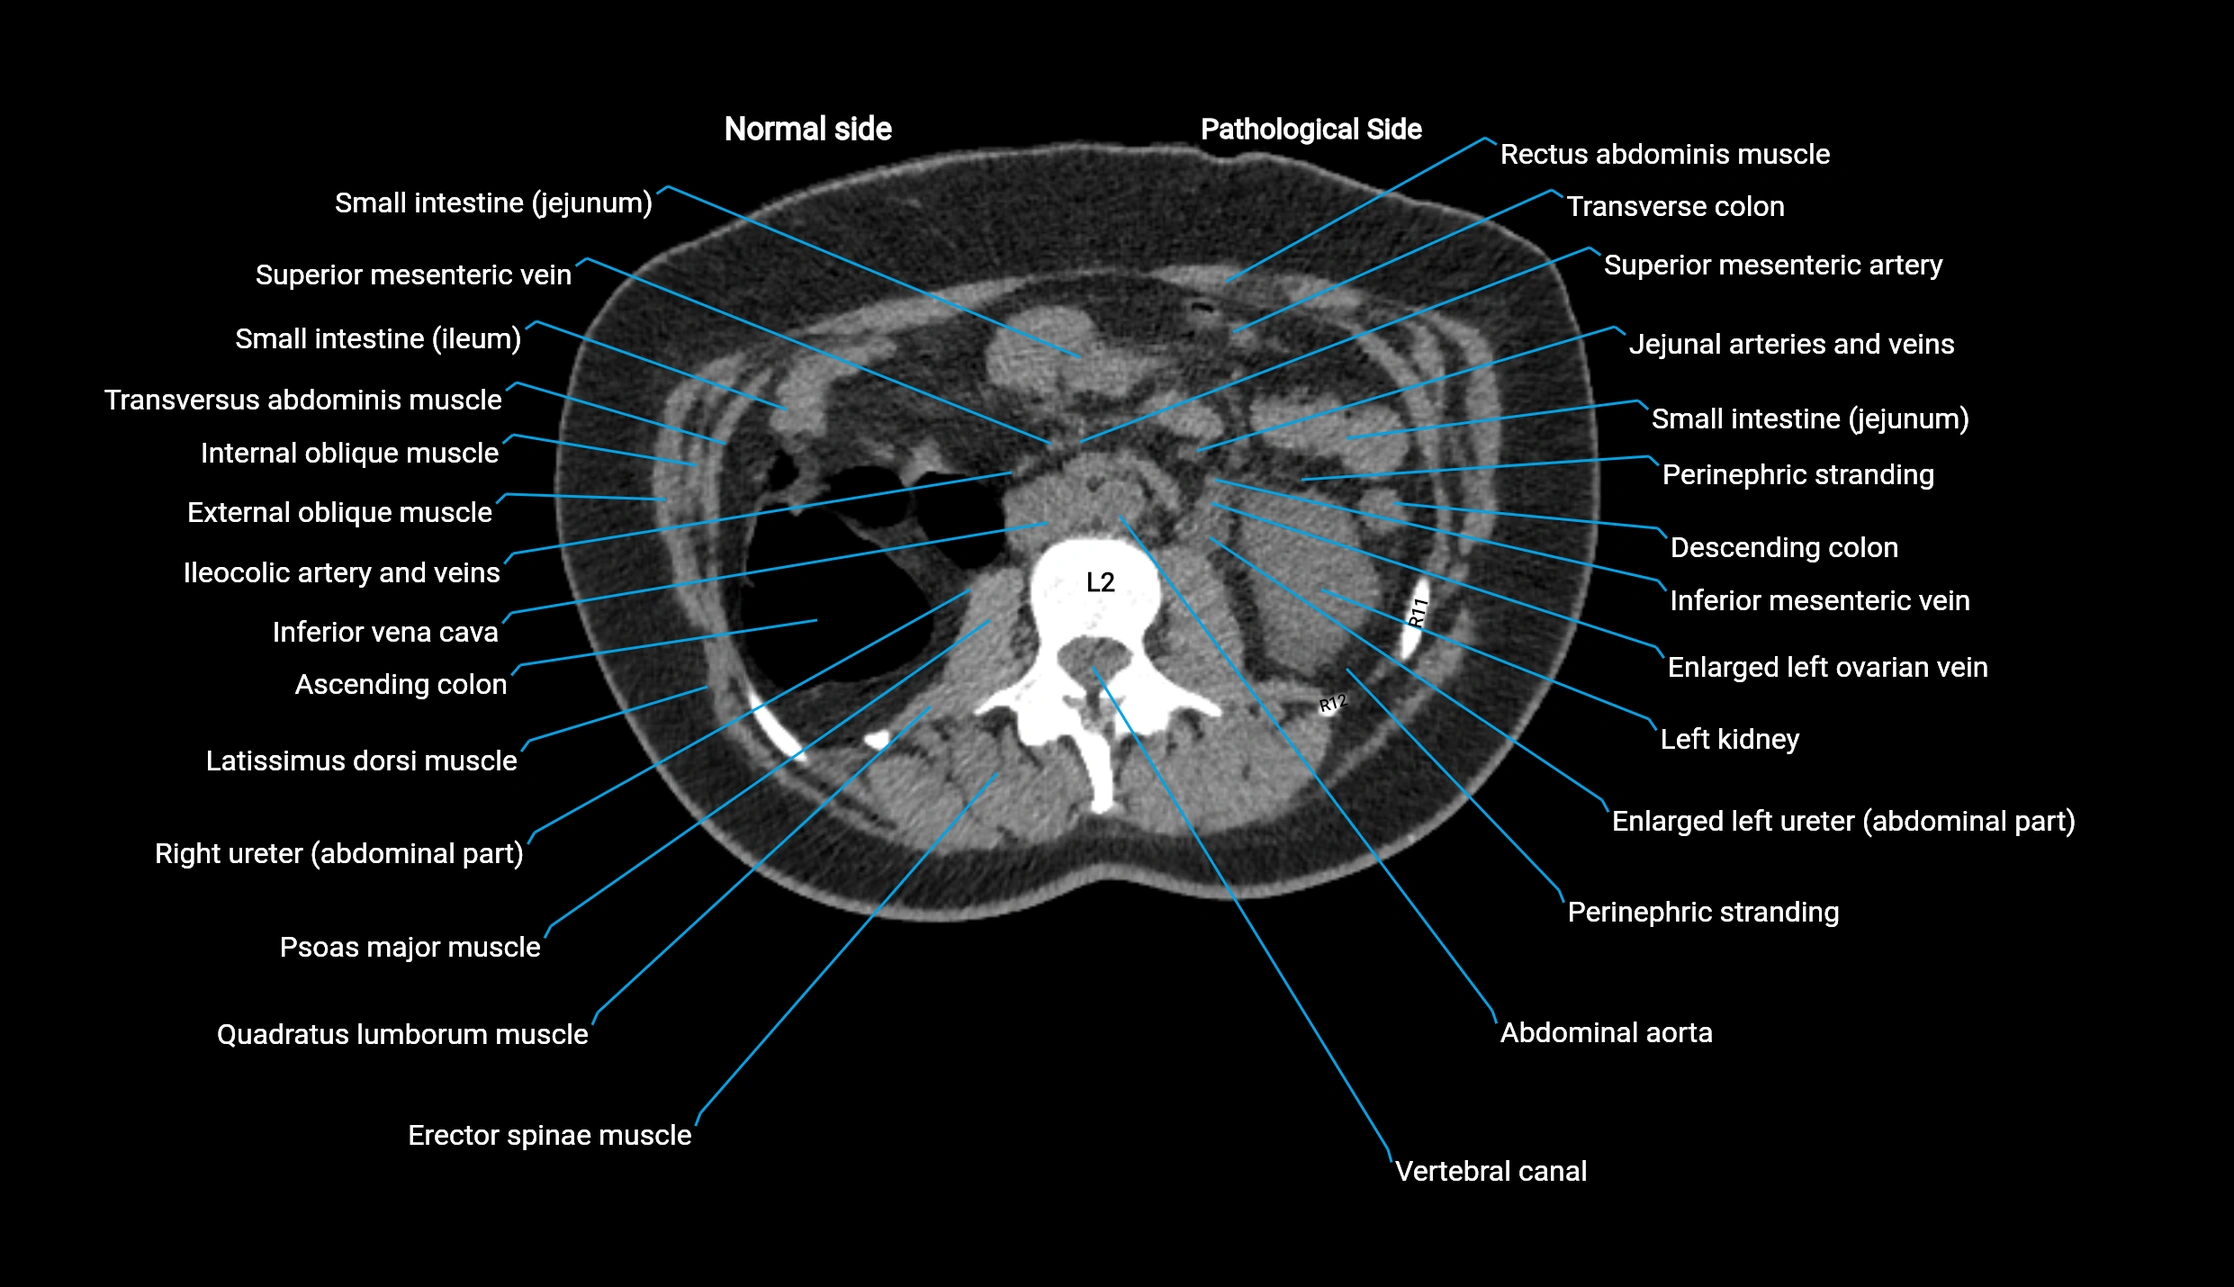

CT image

image